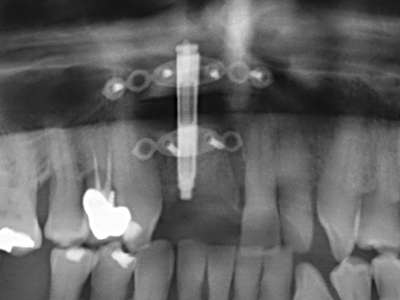

When surgical procedures are performed on bone in the immediate vicinity of sensitive structures such as blood vessels or nerves, rotary instruments pose a significant risk of iatrogenic injury. Piezoelectric devices can be helpful for preparation of bone covers and removal of hard tissue close to nerves, particularly for exposure of nerves after iatrogenic injury but also during nerve lateralization for resective and reconstructive procedures or implant placement (Fig. 17-20). Light contact between the piezotip and the nerve does not generally result in damage but proceeding incautiously with saw-like motions or attachments where a residual bone substrate remains may cause temporary or even permanent nerve damage. However, the risk of damage is considered to be substantially lower than when using saws or milling instruments (Pereira, Gealh et al. 2014).

As shown in the past, basically any bone surgery procedure represents a possible indication for piezo surgery. Thus preparation of the mobile segment in distraction osteogenesis (Fig. 23-25) and sandwich osteotomy uses special attachments without endangering the blood supply to the crestal section, which is essential for the success of both techniques (Gonzalez-Garcia, Diniz-Freitas et al. 2008).

For removal of an implant, a vestibular bone cover that is replaced after removal of the implant screw can be prepared to retain the contour of the alveolar ridge.